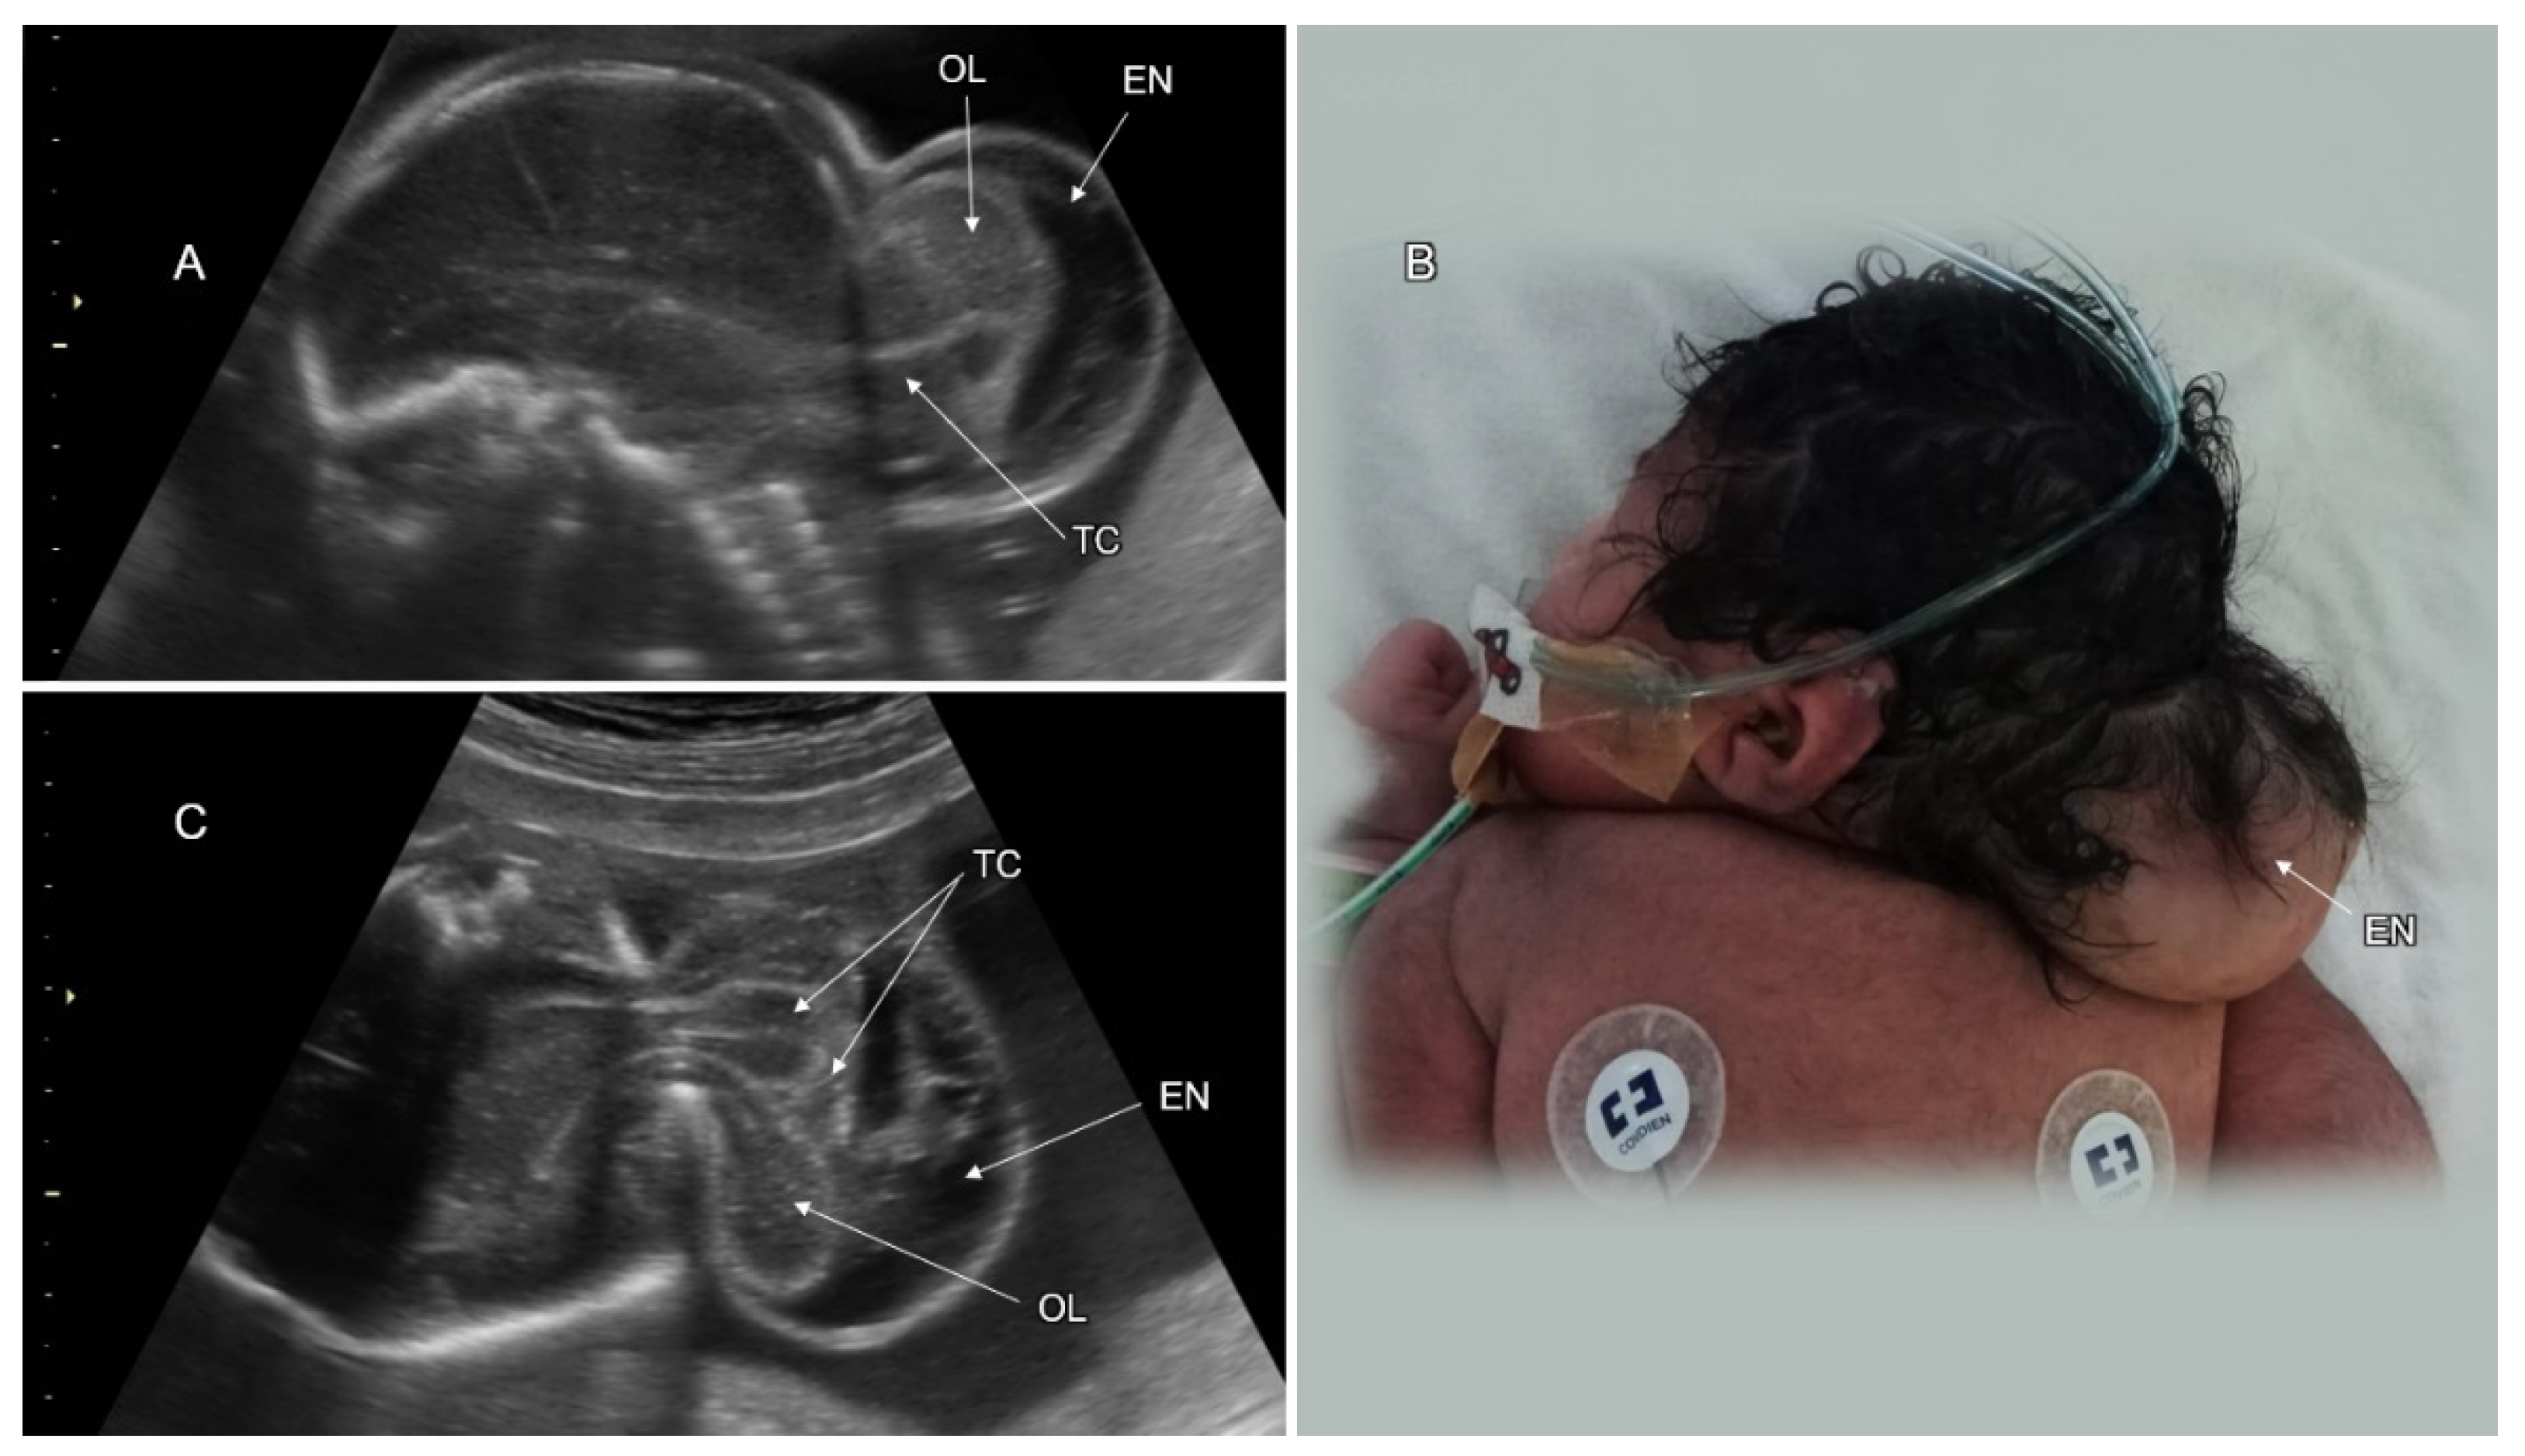

3.1. Cranial NTD

| Cephalocele | 14–18% |

| Childhood mortality:

|